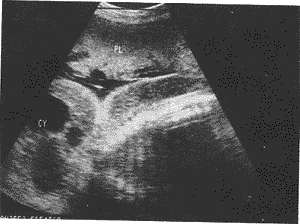

中国超声医学杂志990737 患者女,23岁,妊27周,非近亲结婚,早孕期曾患感冒,服用过抗感冒药,药名不详。 B超所见:胎儿双顶径68mm,头颅光环尚规则,脑中线无偏移,脑室无扩张,枕后探及一70m m×51mm的囊性肿物,形态不规则,边界清,内有纤细光带分隔成多房状,透声好(图1),胎 儿头皮下及背部皮下探及17~19mm宽的低回声暗带(图2),如同胎儿被一层较宽的“茧状物 ”所覆盖。胎儿脊柱、四肢及胸腹腔脏器发育无异常,子宫前壁胎盘厚33mm,2度;羊水池3 0+34+33+28mm,透声好。B超诊断:胎儿畸形,胎儿枕后部淋巴囊肿并头皮及背部皮下水肿。

FH:胎头,CY:囊肿,PL:胎盘

图1 胎儿头部囊肿

CY:胎头囊肿,PL:胎盘

图2 胎儿头部及背部皮下低回声暗带